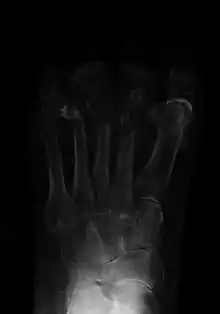

Osteomyelitis (OM) is an infection of bone.[1] Symptoms may include pain in a specific bone with overlying redness, fever, and weakness.[1] The long bones of the arms and legs are most commonly involved in children e.g. the femur and humerus,[7] while the feet, spine, and hips are most commonly involved in adults.[2]

The cause is usually a bacterial infection,[1][7][2] but rarely can be a fungal infection.[8] It may occur by spread from the blood or from surrounding tissue.[4] Risks for developing osteomyelitis include diabetes, intravenous drug use, prior removal of the spleen, and trauma to the area.[1] Diagnosis is typically suspected based on symptoms and basic laboratory tests as C-reactive protein (CRP) and erythrocyte sedimentation rate (ESR). This is because plain radiographs are unremarkable in the first few days following acute infection.[7][2] Diagnosis is further confirmed by blood tests, medical imaging, or bone biopsy.[2]

Symptoms may include pain in a specific bone with overlying redness, fever, and weakness and inability to walk especially in children with acute bacterial osteomyelitis.[7][1] Onset may be sudden or gradual.[1] Enlarged lymph nodes may be present.[11] In fungal osteomyelitis, there is usually a history of walking bare-footed, especially in rural and farming areas. Contrary to the mode of infection in bacterial osteomyelitis, which is primarily blood-borne, fungal osteomyelitis starts as a skin infection, then invades deeper tissues until it reaches bone.[8]